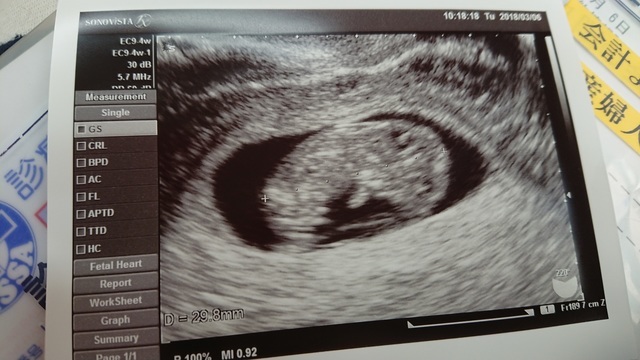

7週0日(7w0d・男の子)|わんちゃん さん(26歳)

エコー写真撮影時のエピソード:

妊娠が発覚した時、初めて撮ったエコー写真です。 当時ドキドキしながら行った婦人科で、ドラマで見たことしかなかったエコー写真を手にした時、とてもうれしい気持ちと、私が母になれるのかという不安と、こんなに小さい赤ちゃんがお腹に居るという感動は忘れられません。

当時つわりもありましたが、赤ちゃんの大きさは7ミリです、と先生からお話されてたった1センチも無い赤ちゃんが生きてる証拠なんだと、それ以降のつわりも愛おしく感じました。